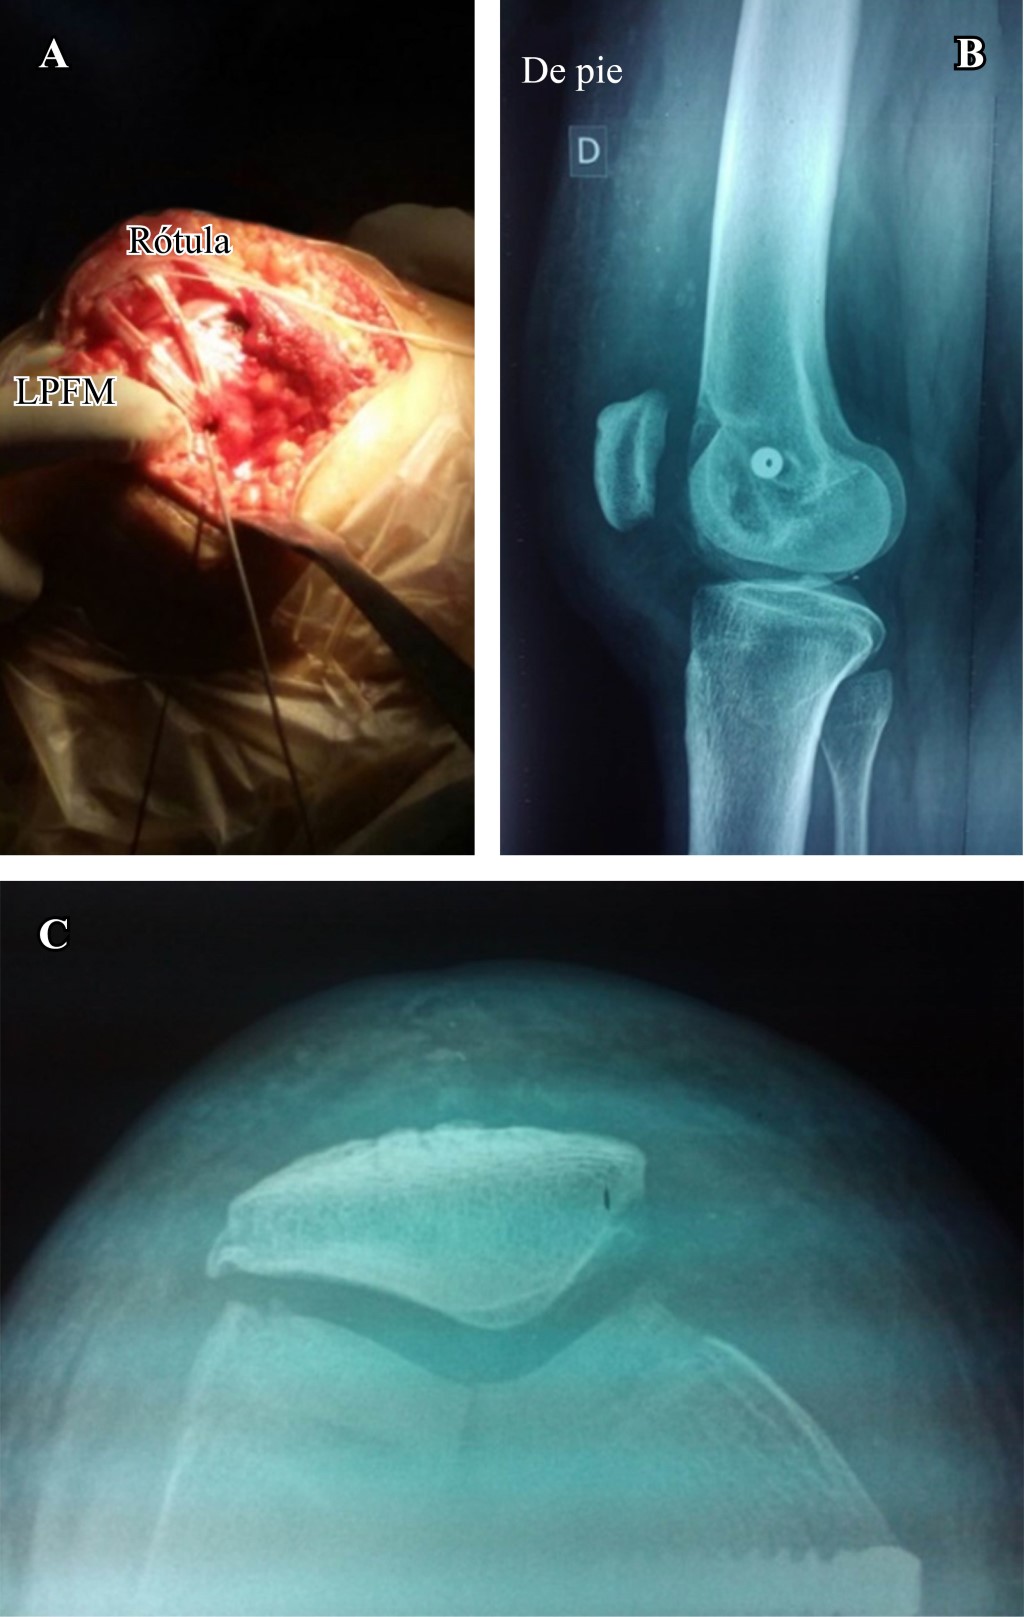

La patela alta es el único factor que podría conducir a una luxación rotuliana en ausencia de otro factor estructural de relevancia. Es una anomalía congénita que resulta de una longitud excesiva del tendón rotuliano. El índice debe medirse en todos los pacientes con trastornos femoropatelares. Podría utilizarse cualquier índice, el más simple es el índice Caton-Deschamps. Este método fue descrito por primera vez por J. Caton en 1976, se modificó en 1982 y es actualmente conocido como el índice de Caton-Deschamps.4,5 La rótula se clasifica como alta si el índice es mayor de 1.2. Un signo indirecto de la rótula alta es la ausencia de la rótula frente a la tróclea en el corte axial de referencia de la tróclea femoral en la tomografía computarizada (Figura 1).

El procedimiento es completado con una reconstrucción del ligamento patelofemoral medial utilizando un injerto de tendón semitendinoso, el cual se tuneliza a través de la rótula y se fija en el punto de isometría femoral según Schottle (Figura 6).15

Realizamos una incisión recta longitudinal en la piel en la cara anterior de la rodilla desde el margen superior de la rótula hasta la articulación femorotibial mientras la rodilla se encuentra en 90o de flexión. Luego, la rodilla se coloca en extensión y se realiza una artrotomía siguiendo las fibras del vasto oblicuo medial, exponiendo 1-2 cm el borde medial de la rótula.

La rótula es evertida para la inspección de posibles lesiones osteocondrales tanto femorales como rotulianas y luego se retrae lateralmente, exponiendo y reconociendo el morfotipo troclear a tratar. Teniendo como objetivo principal disminuir la prominencia troclear y crear un nuevo surco de profundidad y vertientes anatómicos, se realiza la trocleoplastía planificada (Figuras 7 y 8). El procedimiento es completado con una reconstrucción del ligamento patelofemoral medial utilizando un injerto de tendón semitendinoso, el cual se tuneliza a través de la rótula y se fija en el punto de isometría femoral con un tornillo de interferencia.